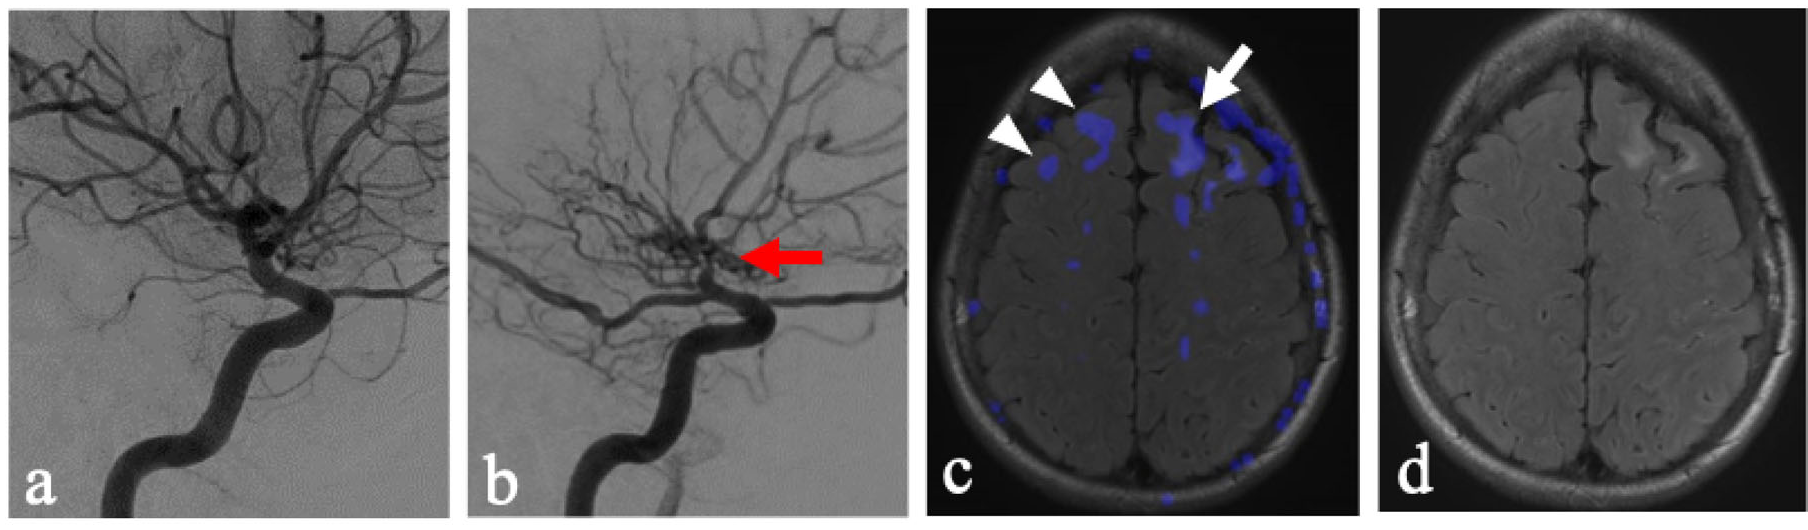

The findings presented suggest that inherent physiological vulnerability may play a role in the ubiquity of leukoaraiosis in this region and demand ischemia to be a key factor in the formation of T2 hyperintensities. While chronic hypertension and microangiopathy are often discussed as the precursor vasculature changes within the deep white matter tracts that, in turn, cause decreased vascular reserve and areas of leukoaraiosis [12], the inherent dynamic physiological vulnerabilities of the vasculature supplying the centrum semiovale may play a key role. This is supported by findings of steal in the centrum semiovale in the side without flow-limiting stenosis (Figure 2). These findings suggest an inherent physiological vulnerability of these regions to possible fluctuations in hemodynamics.

The ability to create subtraction images from ASL CBF maps, which were acquired within the same acquisition, allowed for mapping of augmentation and steal. This provided both qualitative displays of subtle perfusion changes as well as fused overlay on anatomic images (Figure 2c). This allowed for the development of a modified Fazekas score. However, the applicability of this methodology could be limited in other imaging modalities, such as SPECT, DSC perfusion MRI, or CT. The generalizability of these methods in various modalities would warrant future research and may be institutionally dependent. Additionally, while the Fazekas score has demonstrated good inter-rater reliability, such inter-rater reliability for the modified scoring system is not yet assessed.

Figure 2. Adult patients with unilateral vaso-occlusive disease of the left anterior circulation. (a) A right-sided internal carotid artery DSA corresponding to the NFLH. (b) A left-sided internal carotid artery DSA corresponding to the FLH as evidenced by severe supraclinoid internal carotid artery stenosis (red arrow). (c) Axial T2/FLAIR MRI at the level of the centrum semiovale with areas of steal phenomenon overlaid in blue, demonstrating the occurrence of steal within the FLH (white arrow) greater than NFLH (white arrowheads). The steal grades for the right and left hemisphere were 1 and 3, respectively. (d) Axial T2/FLAIR MRI at the level of the centrum semiovale with T2/FLAIR hyperintensities in the left frontal lobe subcortical white matter. The Fazekas for the right and left hemisphere were graded independently as 0 and 2.